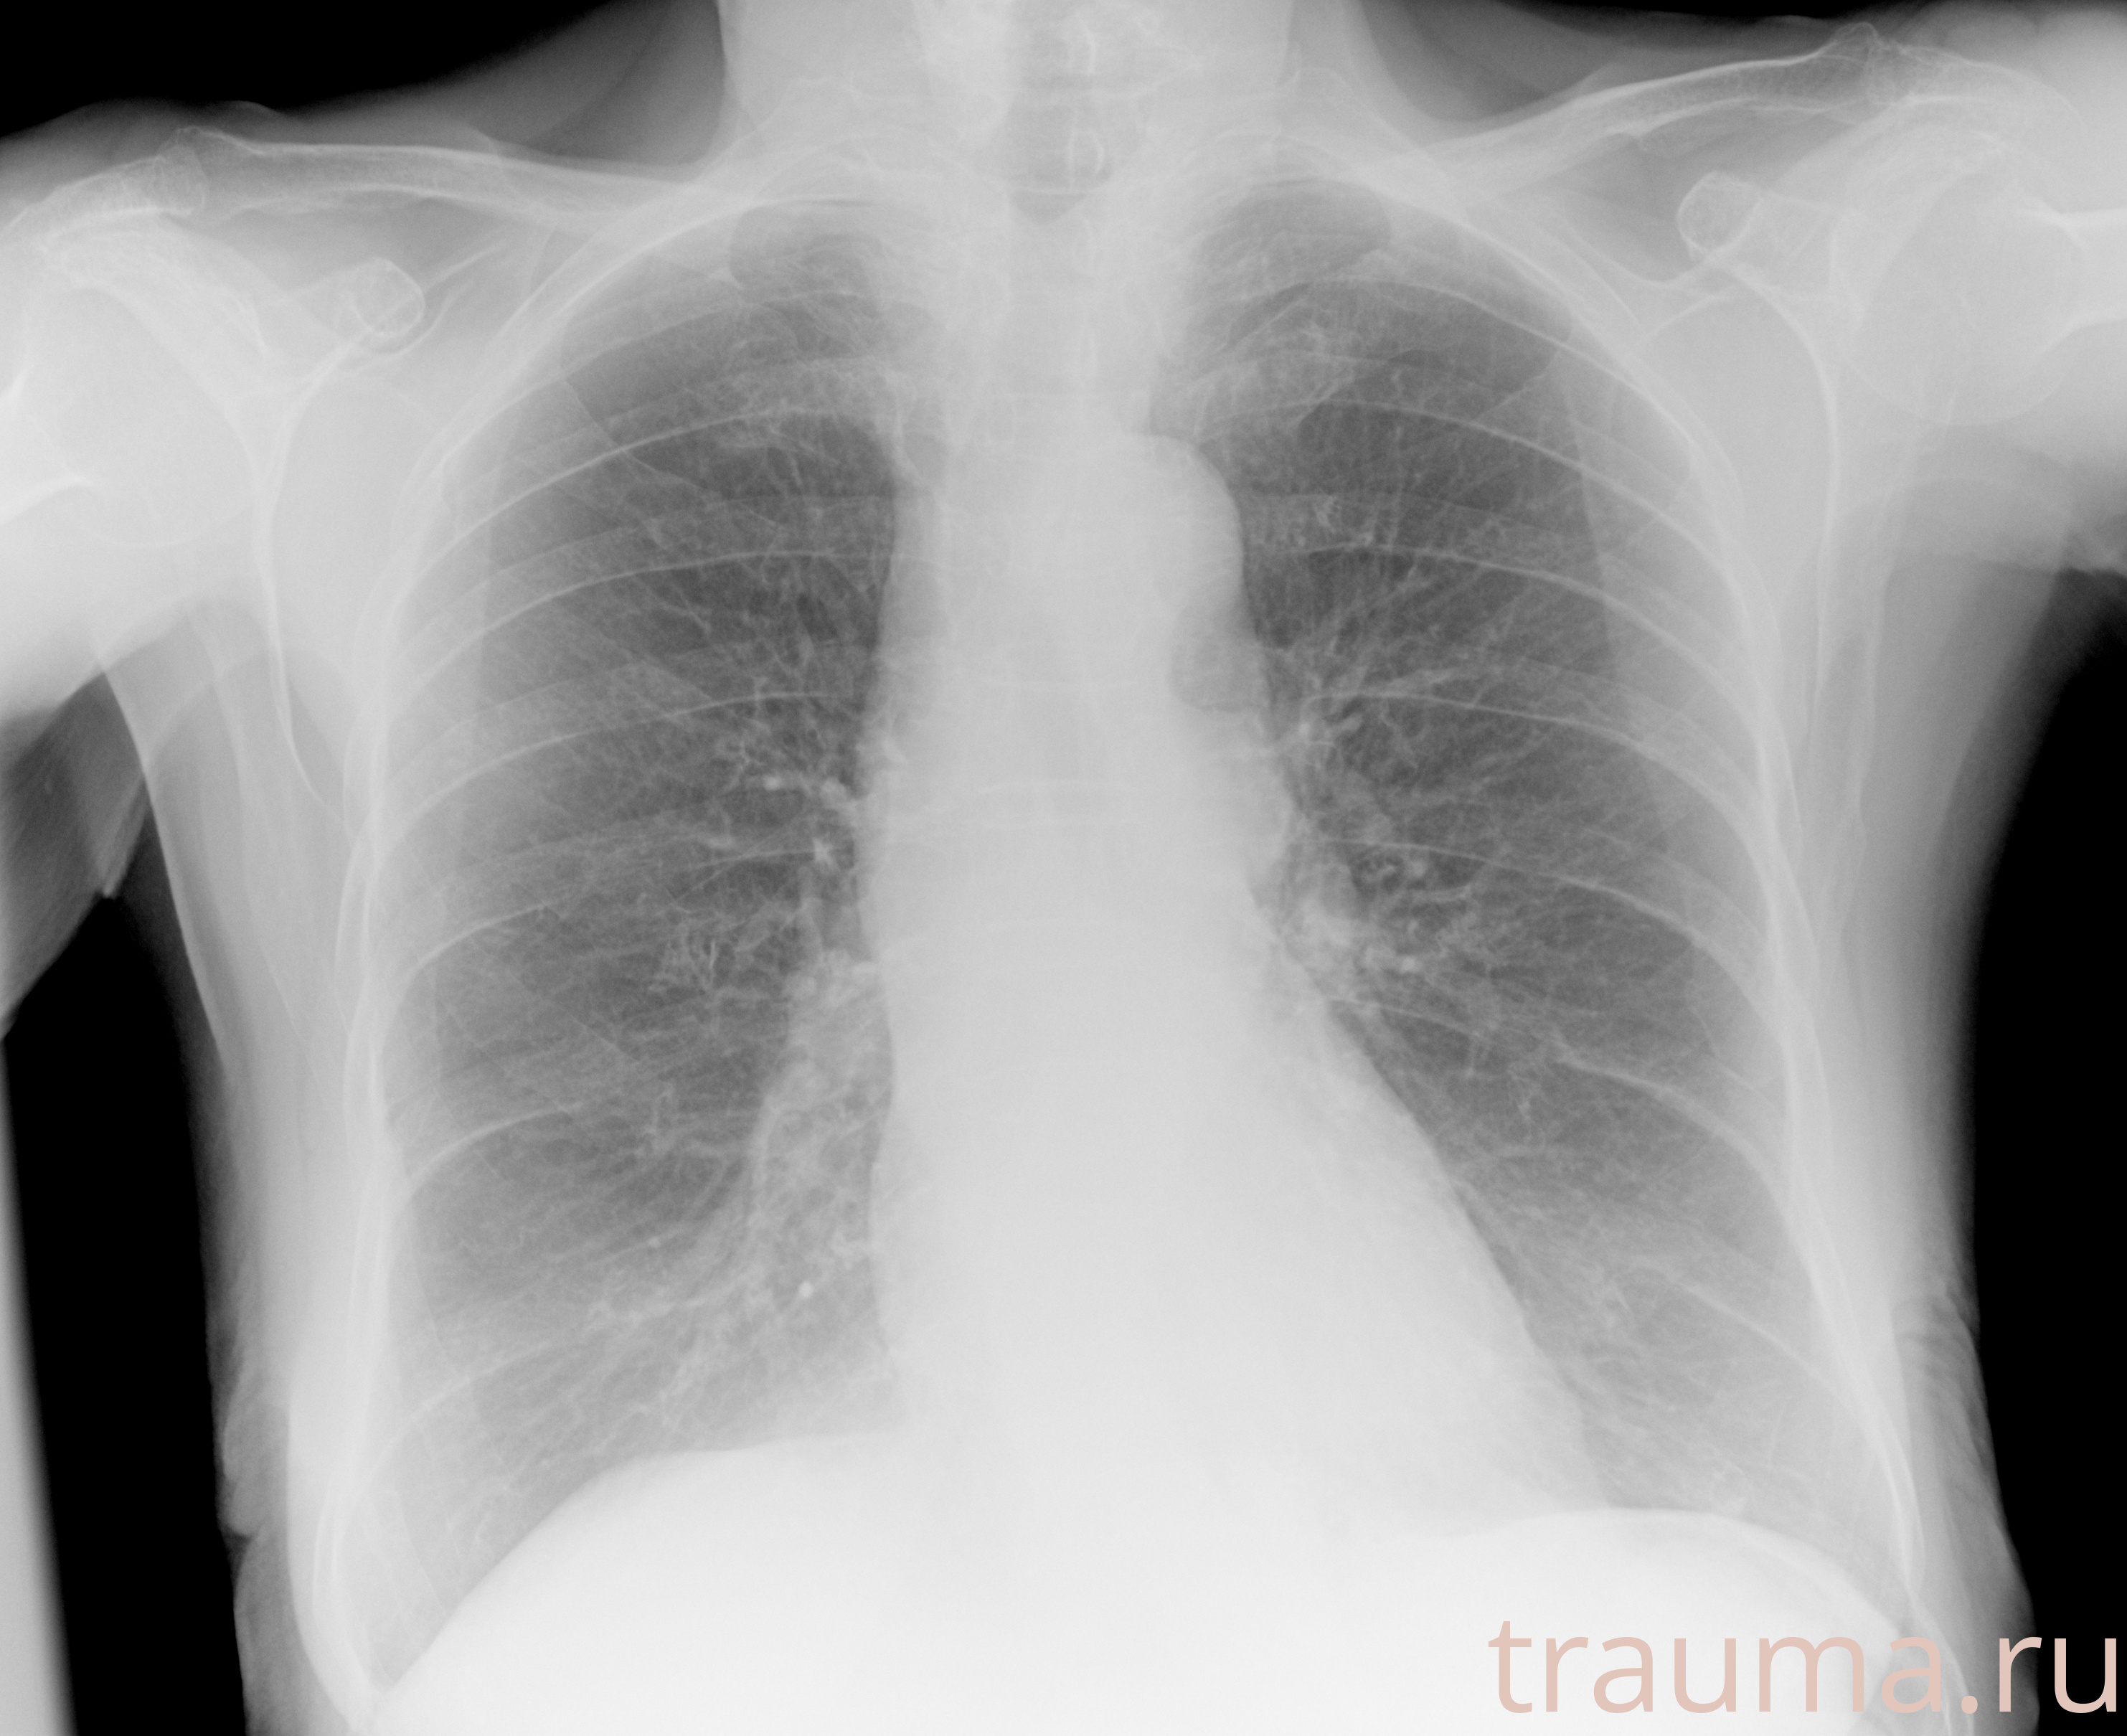

Рентгенограммы

Рентген на дому: по вашему адресу приезжает врач-рентгенолог, травматолог-ортопед с мобильным рентгеновским аппаратом, проводит диагностику травмы или заболевания, делает необходимые рентгенограммы, дает рекомендации по дальнейшему лечению. Получить качественные снимки в домашних условиях возможно благодаря уникальной методике, разработанной МосРентген Центром для института  Склифосовского

Яркость: 1   Контраст: 1   Инвертировать: 0 Увеличение: 1

Перетаскивайте мышь вверх/вниз для контраста, влево/право для яркости. Прокрутка колесом изменяет масштаб. Нажмите Сбросить для возврата к исходному изображению. При увеличении держите мышь в той области, которую хотите рассмотреть.

при переломе шейки бедра и пневмонии от компании МосРентген Центр - партнера Института имени Склифосовского